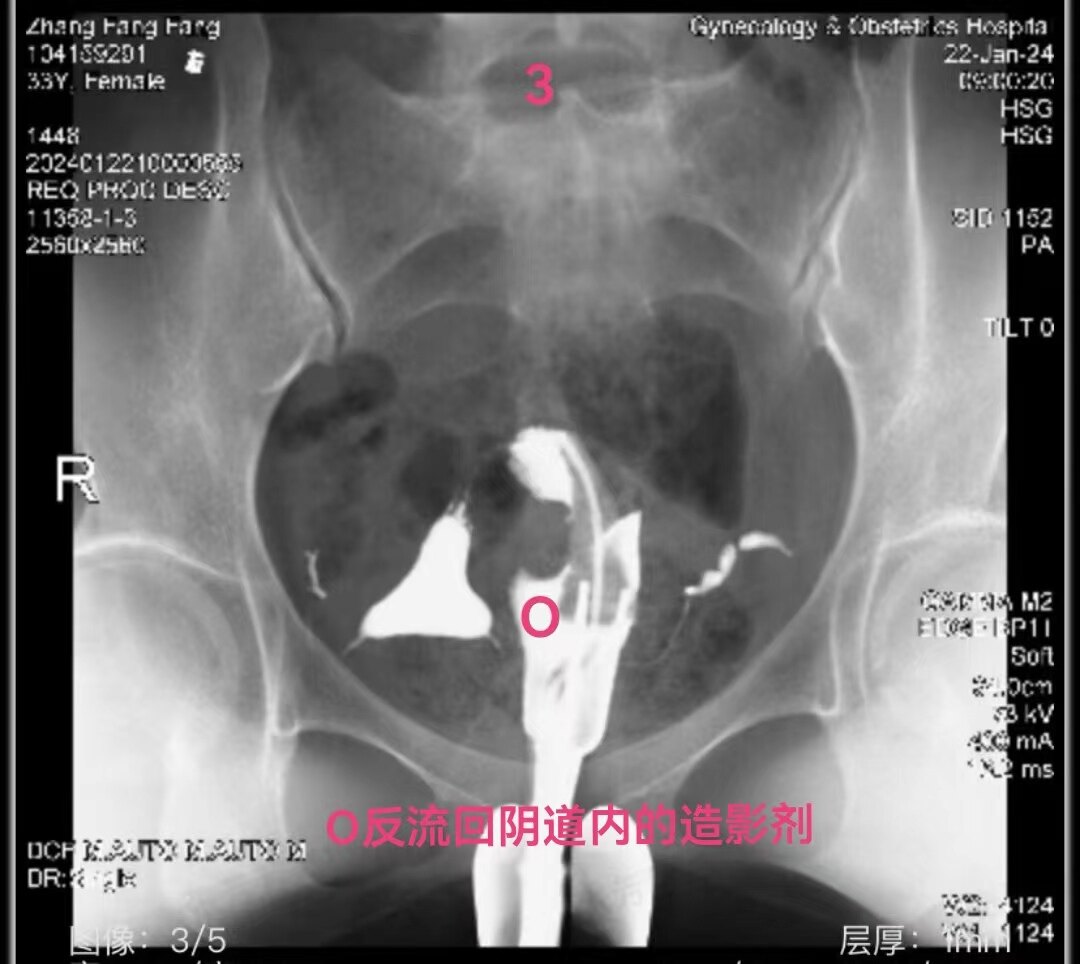

2.jpg

左侧输卵管显影至壶腹部,右侧输卵管显影至峡部。造影剂返回到阴道